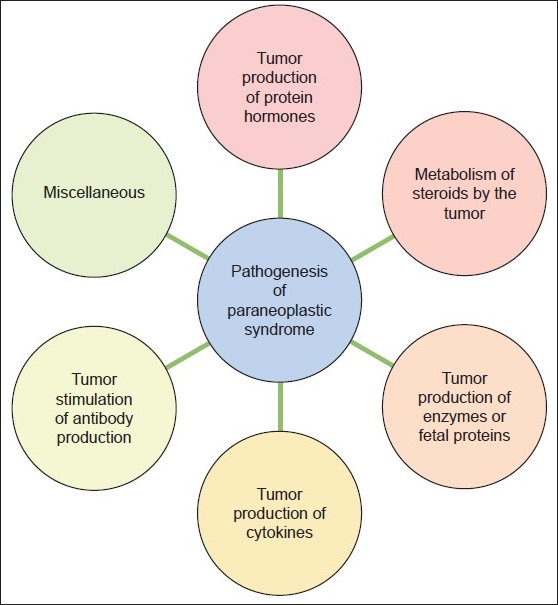

Paraneoplastic Syndromes Of The Nervous System | Ireland| PDF | PPT

www.omicsonline.org

www.omicsonline.org paraneoplastic syndromes nervous system symptoms syndrome ppt pdf common pathology disease cancer cell carcinoma oral treatment most squamous associated